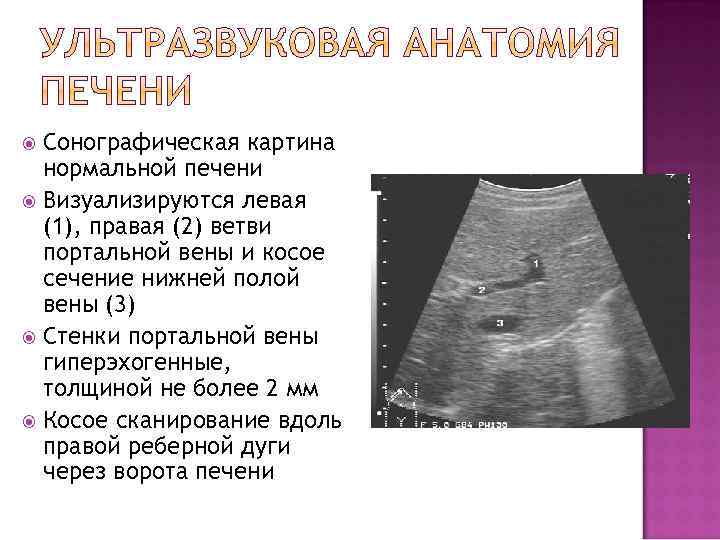

Сонографическая картина нормальной печени Визуализируются левая (1), правая (2) ветви портальной вены и косое сечение нижней полой вены (3) Стенки портальной вены гиперэхогенные, толщиной не более 2 мм Косое сканирование вдоль правой реберной дуги через ворота печени